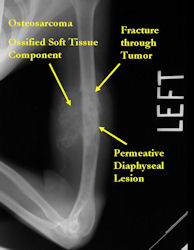

There are 3 radiographic presentations for osteosarcomas, depending upon the amount of osteoid/ossification and calcium deposition:

- Mixed sclerotic and lytic, permeative lesion most common radiographic presentation

- Purely lytic, permeative lesion: little osteoid production and/or minimal calcium deposition in osteoid

Conventional osteosarcomas are permeative lesions on plain radiographs (borders of the lesion cannot be clearly delineated)

- Wide zone of transition from lytic/sclerotic areas of tumor to normal bone

- Makes borders of lesion hard to define

- Rarely (10%) arise from the diaphysis

- Most conventional osteosarcomas (90-95%) extend through the bone into the soft tissues and form a soft tissue mass outside of the bone